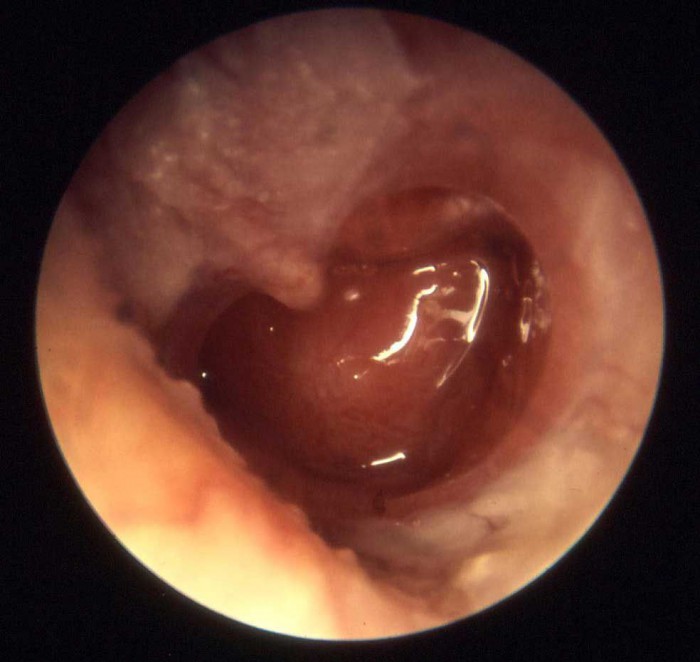

Вот как может выглядеть барабанная перепонка при экссудативном среднем отите.

Сначала врач проводит отоскопию у маленького пациента. Этот метод направлен на изучение состояния барабанной перепонки.

Её изменения могут варьироваться от незначительных до значительных:

- затемнение перепонки;

- выпуклость или вогнутость;

- приобретение перепонкой голубоватого оттенка;

- усиление;

- распространение до такой степени, что видна жидкость (в этом случае можно даже разглядеть, насколько плотный на данной стадии экссудат).